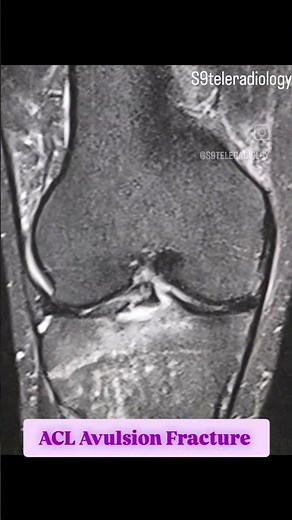

Top suggestions for ACL Avulsion Fracture |